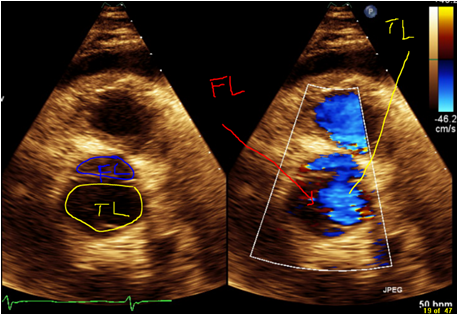

Case Presentation: A 57-year-old African-American male, with past medical history of nonischemic cardiomyopathy, moderate aortic insufficiency, HTN, and cocaine abuse presented to the emergency room with complaints of shortness of breath (SOB), and chest pain (CP). He admitted to using cocaine on his birthday party, which was 5 days ago. After using cocaine he started having freezing substernal CP which were 5/10 in intensity, intermittent, nonradiating and associated with feeling of SOB. The patient’s CP resolved with sublingual nitroglycerin. In the last 17 months patient had been admitted in hospital four times with complains of SOB and CP with the following chronologic diagnosis: HTN emergency, Atrial flutter, Acute HF exacerbation. Prior CT Chest with contrast did not show any AoD. Cardiac catheterization done in the last admission showed no significant coronary artery disease. Cocaine has been reported positive in all these admissions. On physical exam he had grade two systolic murmurs at base; mild crackles at lung base, no pedal edema or jugular vein distension. ECG showed no acute findings. Serial troponins three times were normal. Chest x-ray showed cardiomegaly with new wide mediastinum. Trans-thoracic echocardiography showed unchanged aortic regurgitation and Stanford type A AoD. CT chest confirmed AoD type A with dissection propagating to abdominal aorta. Patient immediately was transferred to a tertiary center. He underwent emergency repair of aortic dissection. Post surgery, he recovered well and was discharged after three days of hospital stay.